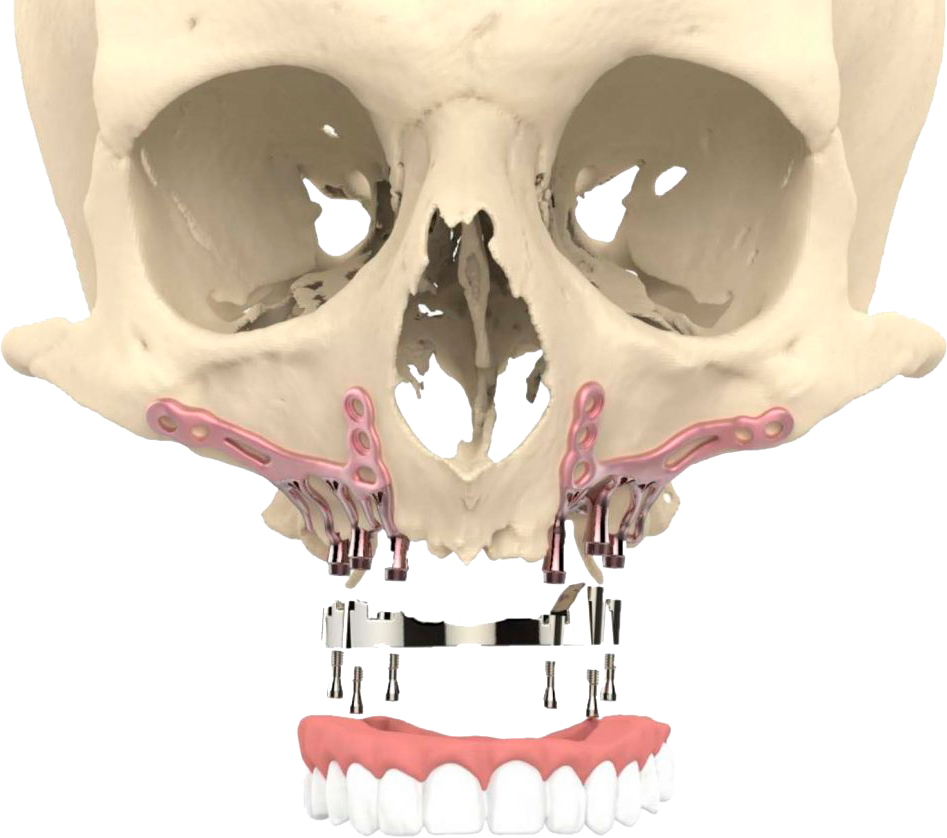

Los implantes subperiósticos o yuxtaóseos son dispositivos médicos utilizados en cirugía maxilofacial y dental para reemplazar dientes perdidos o para estabilizar prótesis dentales.

Estos implantes dentales se colocan debajo del tejido óseo que recubre la mandíbula o el maxilar superior, conocido como periostio, y proporcionan una base sólida y estable para la fijación de los dientes artificiales.

A diferencia de los implantes dentales convencionales que se insertan directamente en el hueso, los implantes subperiósticos se colocan debajo del periostio para aprovechar la mayor cantidad posible de superficie ósea disponible y proporcionar una mayor estabilidad.

Una vez preparado el lugar de colocación del implante dental, se colocará el implante subperióstico debajo del periostio y se asegurará con tornillos especiales.